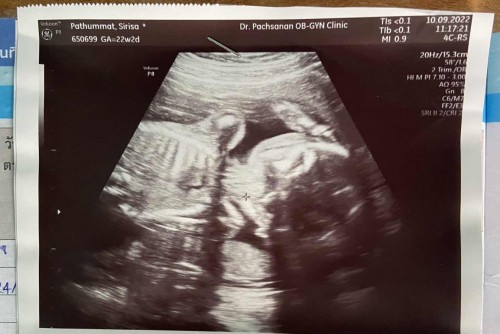

คุณแม่ดูออกมั้ยคะว่าน้องนอนอยู่ในท่าแบบไหน คุณหมอไม่ได้บอก และ เด็ก22w2d หนัก420gถือว่าตัวเล็กมั้ย

เด็กอายุ22w 2d น้ำหนัก420g ถือว่าน้ำหนักน้อยมั้ยคะ อยากรู้ว่าเด็ก22w น้ำหนักมากได้สุดเท่าไร น้อยสุดเท่าไร

ดูไม่ออกค่ะว่าท่าอะไร🥰 น้ำหนักตามเกณฑ์ค่ะ ถามคุณหมอที่ฝากครรภ์มา น้ำหนักเท่านี้คือตามเกณฑ์ของอายุครรภ์เท่านี้ค่า ของเราน้องหนัก400กรัมค่า

ของเรา22วีค5วัน300กรัมเองจ้าเดียวพอ6เดือนขึ้นไปน้องก้อเริ่มไหย่ขึ้นค่ะ

บ้านนี้20w2dน้ำหนัก452กรัมค่ะถ้าหมอบอกว่าปกติก็ไม่เป็นไรค่ะ🥰

บ้านนี้22วีค5 504 กรัม แม่ได้ไป2โล ลูกขึ้น 2 ขีด

ดูจากรูปเหมือนข้างหลังเลยค่ะ

บ้านนี้21วีค2วัน 395จ้า